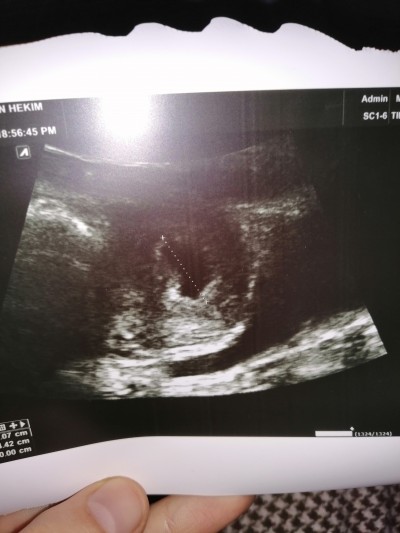

Kese Var Bebek Yok

Kese Var Bebek Yok.

6 0 da kese var bebek yok boyle olup sonradan bebegin kalp atisini duyan var mi hamilelik donemi genel